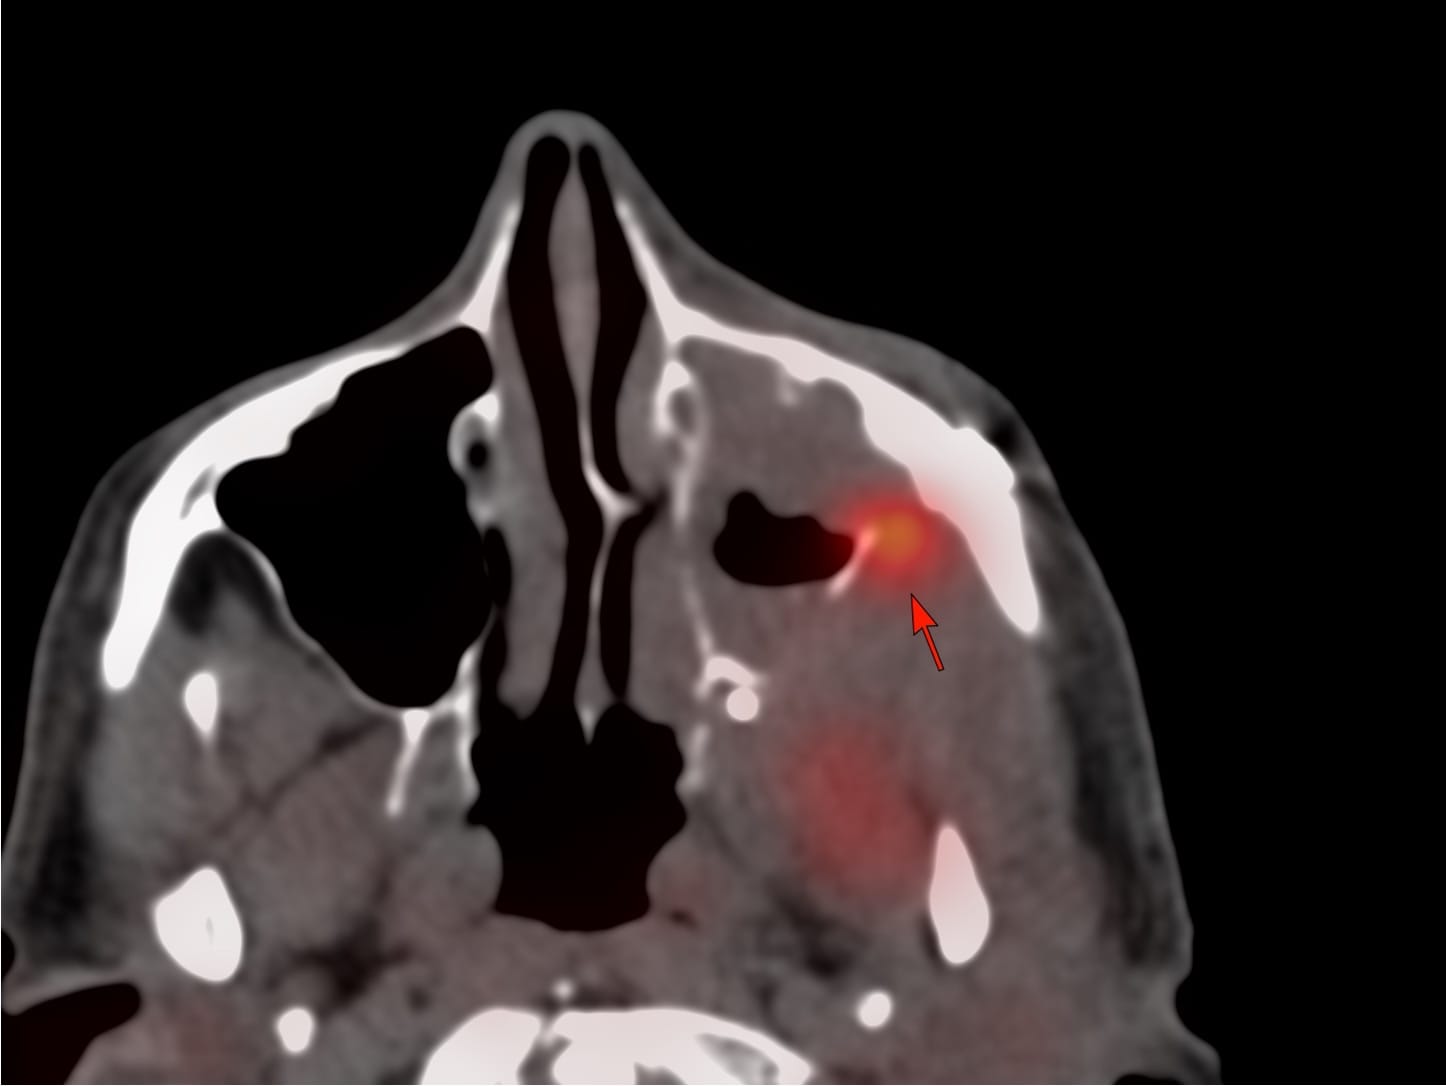

55-yrs old treated buccal ca with focal soft tissue and uptake on a follow-up PET in the left posterolateral maxillary sinus wall was referred for a CT guided biopsy.

Findings: Focal uptake posterolateral maxillary sinus wall

Lesion Biopsied: This lesion

Diagnosis: Squamous cell carcinoma, recurrence